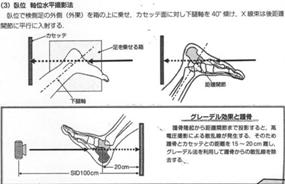

④ 足関節踵骨部・・・撮影は足関節斜位4方向撮影が基本となる。ポジショニングには無理を強いらないように注意する。足関節側面像にはクロステーブル撮影法も有用である。踵骨骨折を疑った時にはまず側面像を撮影し評価する。骨折のある踵骨軸位像撮影法は踵骨軸位像が歪む40度斜入撮影は止め、側面撮影を行ったポジショニングのままで軸位像が得られる、受光面にX線を直交入射するクロステーブル撮影法を用いる。この撮影法は脛骨最下端部と足舟状骨粗面を結ぶラインを水平X線に平行とするだけで歪みの無い踵骨軸位像が“患者さんに痛みを与えることが無く”得られる非常に有用で簡単な撮影技術である。グレーデル効果にて散乱線除去を行うことから低い管電圧50数kvが利用でき40度斜入法にあるヒール効果も現れず踵骨骨梁鮮明な軸位像を描出することが出来る。骨折の有る距踵関節撮影は元九州大学病院の榊和宏先生が第11回ISRRT幕張大会で発案されポスター展示最優秀賞の評価を得られた両側同時距踵関節撮影法を紹介します。非常に有用で“患者さんに優しい撮影法”であります。踵骨骨折の基準撮影は踵骨側面像が撮影され画像読影後そのままの側面撮影ポジションで軸位像を撮影する。最後に両側同時距踵関節像を撮影する。この踵骨3方向撮影は“患者さんに無理を強いらない優しい撮影技術”である。

踵骨側面像撮影 軸位撮影法

軸位撮影法

(脛骨下端-足舟状骨粗面ライン2横指踵側へ水平X線入射)